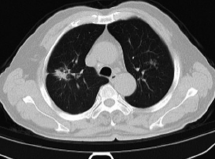

LDCT全名叫低剂量螺旋CT,它跟普通CT的区别就是降低了X线的剂量,那LDCT有什么厉害的呢? LDCT能检查出比一粒米饭还小的病变,而X线一般只能检出像一角硬币那么大的病变,因此它能及早的发现早期肺癌。 很多人做检查都会担心辐射的问题,LDCT比常规CT的辐射剂量降低了75%以上,它能用很低剂量的X线形成清晰的图像。 LDCT这么厉害,会不会检查费用很高呀?这一点大家不用担心,它的检查费用和普通CT的检查费用是差不多的。 目前南京市胸科医院已开展LDCT筛查多年,有丰富的诊断经验,且当天就可以检查并取结果。 防大于治,什么样的人要做肺癌筛查呢? 如果你是高危人群,那这里建议你一年筛查一次。 年龄在50岁以上, 且符合以下一项危险因素: ①吸烟≥20包/年,其中也包括曾经吸烟,但戒烟时间不足15年者; ②被动吸烟者; ③有职业暴露史(石棉、铍、铀、氡等接触者); ④有恶性肿瘤病史或肺癌家族史; ⑤有COPD(慢性阻塞性肺疾病)或弥漫性肺纤维化病史。 在所有的癌症中,肺癌的发病率和病死率最高,我国每年新增肺癌人数就超过了70万。 然而更可悲的是,由于肺癌早期症状不明显,三分之二的肺癌患者发现患病时已经是中晚期,其中大多数患者都丧失了手术机会。 如果肺癌能及早发现,那生存率将大大提高,据研究表明早期肺癌(I期肺癌)5年内的生存率高达80%,而晚期肺癌5年内的生存率不足20%。因此肺癌筛查的价值非常大! 由于胸片检查的缺陷和不足,不能清晰显示肺部较小病变,会延误病情,所以在这里建议大家做肺癌筛查一定要选择LDCT。 参考文献: [1]蒋佳霖,陈珍,林姹姹.低剂量CT在肺癌筛查中的应用[J].北京医学,2020,42(03):250-251+253. [2]李治中.深呼吸[m].清华大学出版社,2018,27-31. 图片来源: 南京市胸科医院—呼吸无小事 知网期刊